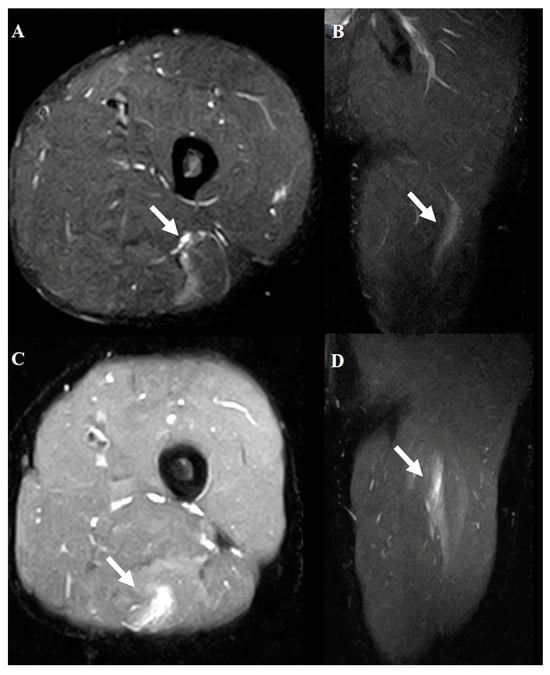

2.4. Hamstring Muscle Diagnosis Using MRI

3.3. Agreement Between US and MRI and Clinical Relevance of Injury Location